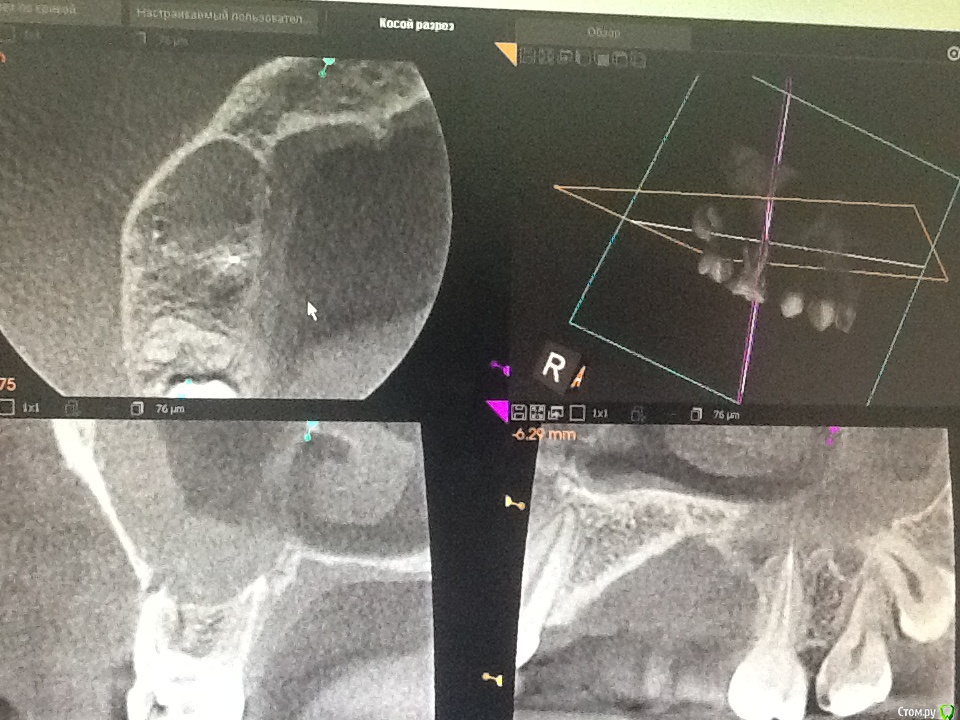

Сева северный Опубликовано 25 ноября, 2015 Поделиться Опубликовано 25 ноября, 2015 (изменено) Этот зуб будет мучить пациента если эндо проведено неудачно, не получилось, не удалось и т д. Если с эндо все в порядке, на реколле положительная динамика, я вот уверена, что там срок службы больше 10 лет, при условии изготовления хорошей коронки . Если не сложно, ответьте , пожалуйста , через сколько после удаления сделан снимок, здесь явно не через 2 неделиПовторное Кт было сделано через 6 месяцев.. Для сохранения обьемов кости, удаление было сделано с костной пластикой. Сейчас, предстоит имплантация. терапевт...хирург и ортопед .на один и тот же зуб смотрит по разному...Это данность.Это как в анекдоте... Когда родители заходят в комнату где их сын занимается любовью с девушкой. мысли вслух всех четверыхПарень: Ну все застукали...Девушка: Теперь он точно на мне женится..Мать: Ну как он закинул ногу.... ему же так неудобно..Отец: Да ..вырос сынок... пора покупать мотоцикл. Изменено 25 ноября, 2015 пользователем Сева северный Ссылка на комментарий

Л Ю С Я Опубликовано 25 ноября, 2015 Поделиться Опубликовано 25 ноября, 2015 Повторное Кт было сделано через 6 месяцев.. Для сохранения обьемов кости, удаление было сделано с костной пластикой. Сейчас, предстоит имплантация. терапевт...хирург и ортопед .на один и тот же зуб смотрит по разному...Это данность.Может быть и так. Но должны быть положительные результаты. Когда я показываю свои результаты эндо после 2,4 лет наблюдения хирургам, которые были категорически против лечения, доводы такие: нуачерез 10 лет? А Вы можете гарантировать , что не будет переимплантита через 10 лет? 1 Ссылка на комментарий

Сева северный Опубликовано 25 ноября, 2015 Поделиться Опубликовано 25 ноября, 2015 Может быть и так. Но должны быть положительные результаты. Когда я показываю свои результаты эндо после 2,4 лет наблюдения хирургам, которые были категорически против лечения, доводы такие: нуачерез 10 лет? А Вы можете гарантировать , что не будет переимплантита через 10 лет?я же ответил....все индивидуально... в вашем случае синус ответил на воспаление незначительным увеличением обьема слизистой....у меня затемнение всей пазухи. Ссылка на комментарий